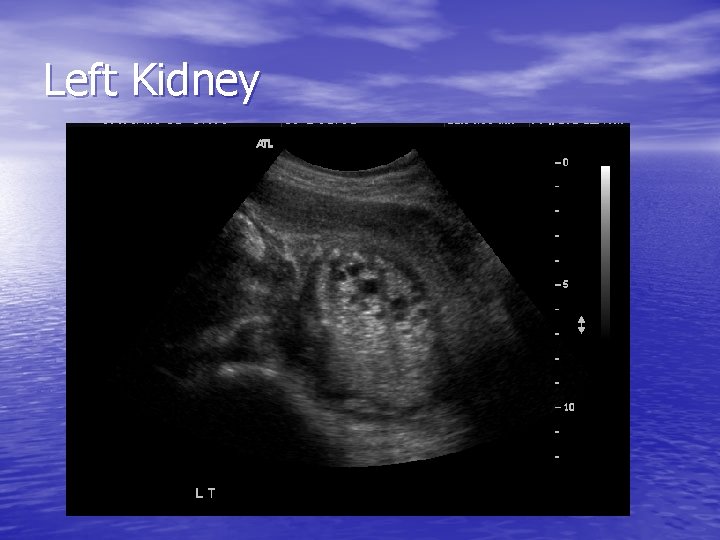

Left Kidney